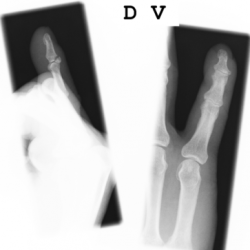

4) Strecksehnenverletzungen der Hand

Die Strecksehnen im Bereich der Hand werden über viele Zügel und Querverbindungen gesichert, somit sind Strecksehnenverletzungen deutlich weniger problematischer als Beugesehnenverletzungen. Im Streckerbereich ist häufig, trotz Verletzung der Sehnenstruktur, noch eine aktive Streckung über Seitzügel möglich. Bei sicherer Durchtrennung eines Teils des Streckapparates wird häufig eine direkte Naht durchgeführt, die Nachbehandlung ist weniger aufwendig und kürzer als im Bereich der Beugesehnen.Strecksehnenverletzungen in Höhe des Endgelenkes sind relativ häufig, auch im Rahmen von spontanen Rissen durch forcierte kraftvolle Beugung im Endgelenk möglich. Hier kann meist eine konservative Behandlung mit Ruhigstellung in einer speziellen Plastikschiene erfolgen. Diese Plastikschiene (Stack'sche Schiene) muss dann über 6-8 Wochen konsequent getragen werden, damit der Strecksehnenansatz in Höhe des Endgelenkes vernarben kann.

Röntgenbilder